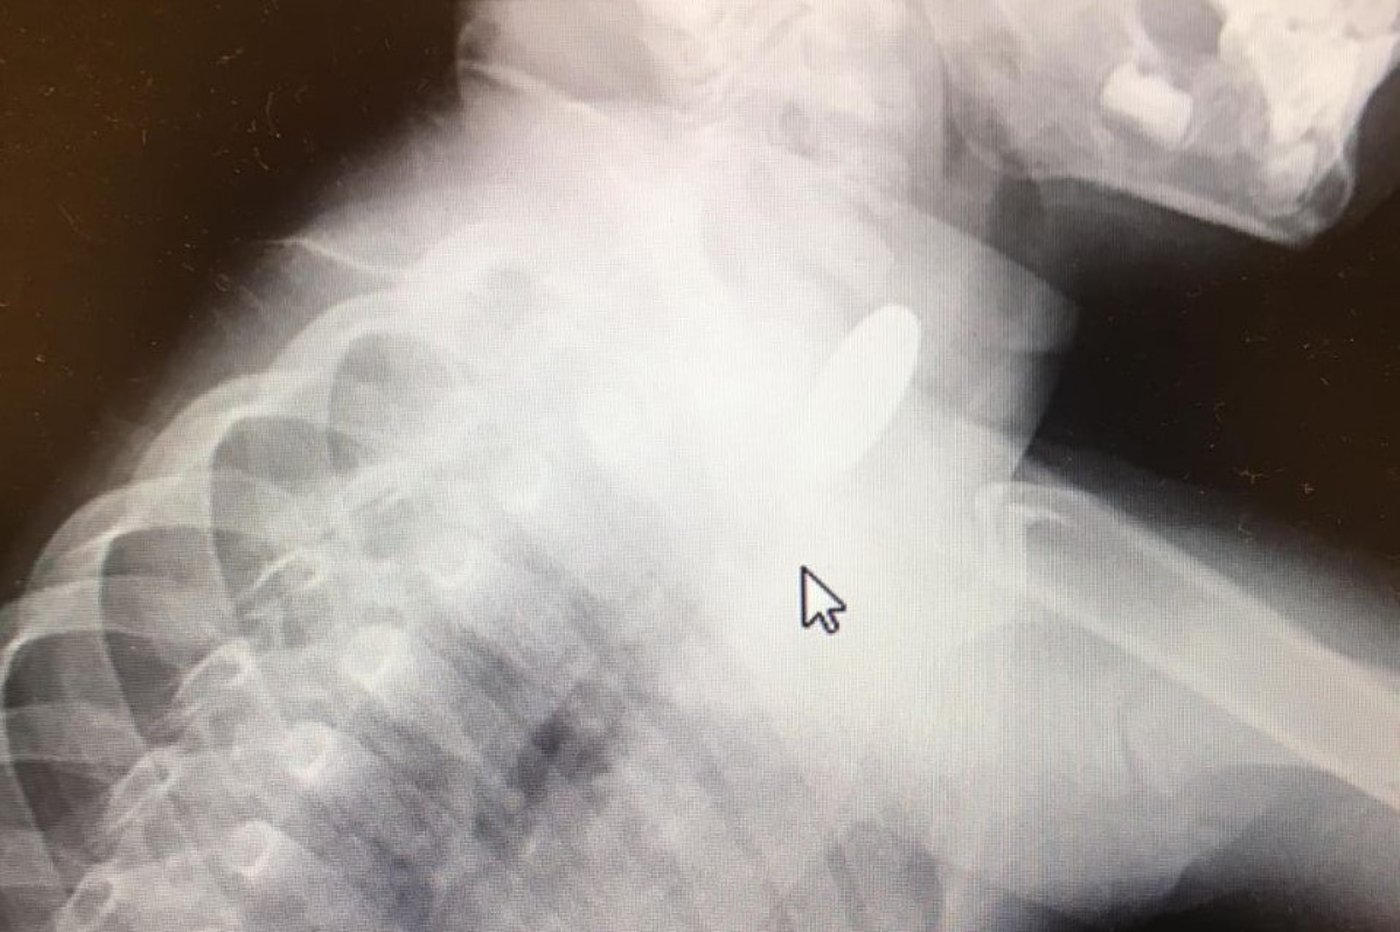

עם הגעתו של הילד לבית החולים הוא הוכנס לצילום רנטגן ושם ראו בבירור מטבע בקוטר 22 מ"מ שעמד בחלק העליון של הושט.